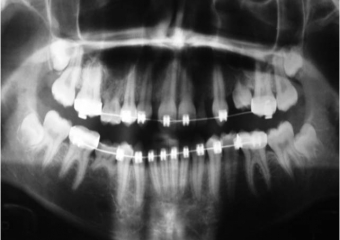

Raio X inicial